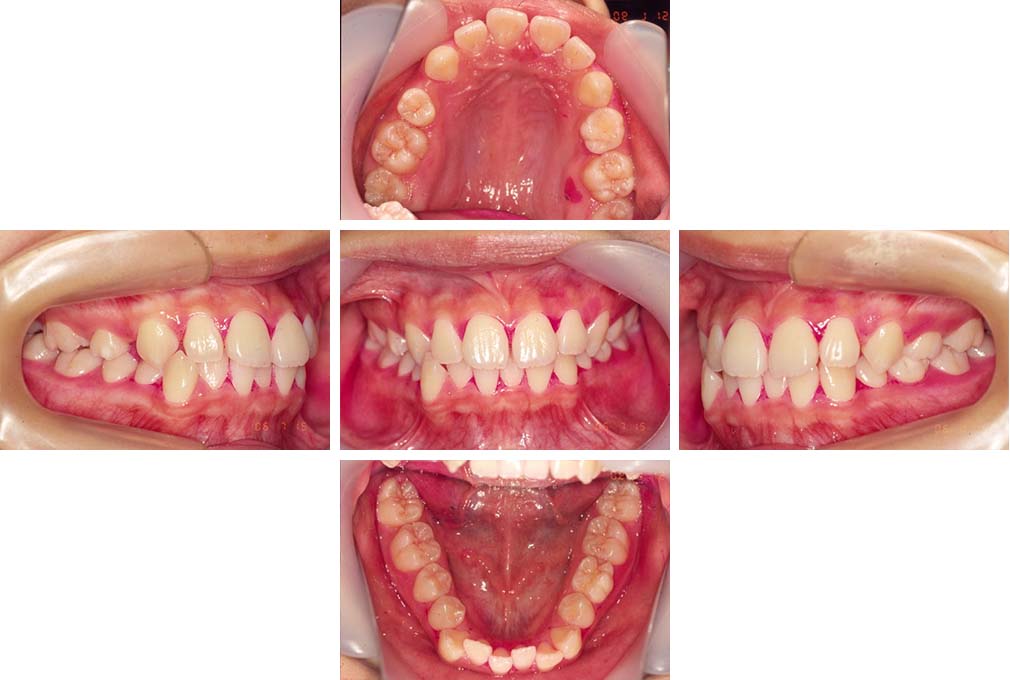

CASE:03

上下顎前突

初診時年齢 18歳4か月

性別 男性

治療費の目安 105万円程度(治療開始時)

歯列の乱れは著しくなく上顎右側側切歯が捻転し口蓋側へ転位していた。また、問診の中で患者さんから最も重視する治療結果として口元の突出の改善の申出があった。下顎が後退した上顎前突傾向ではあったが著しいものではなかった。上下顎前突と診断し上下顎小臼歯抜歯を行っていただき、上下顎舌側マルチブラケット装置を使用して、矯正用アンカースクリューを併用して動的治療を行った。上下顎前歯の後退を十分行い口元の突出感も改善した。治療後10年1か月の来院時には口元の突出感が再発することもなく、下顎前歯の少しの唇舌的なずれはあったが歯列は安定していた。動的治療期間2年2ヵ月間。

治療前

18歳4ヵ月

治療後

動的治療期間2年2カ月間

20歳10か月

10年経過

動的治療終了後10年1カ月

30歳11か月